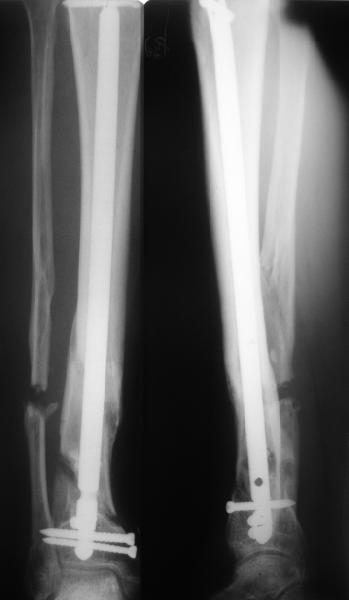

А я бы хотел еще раз подчеркнуть ключевую роль вмешательства на малоберцовой кости в подобной ситуации. В приведенном примере при открытом переломе произошла потеря большого фрагмента большеберцовой кости. Фиксация интрамедуллярным гвоздем с одним блокирующим винтом проксимально и одним дистально. Плюс стабильный остеосинтез малоберцовой. Консолидация за три месяца без костной пластики в условиях ранней нагрузки.